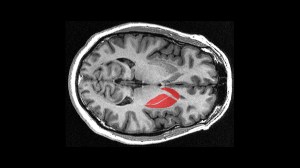

Article: How the brain triggers action

EPFL scientists have identified specific neurons in the striatum that contribute to driving motivated behaviors like movement. The work may help in designing new ways of treating disorders like Parkinson’s disease in the long term. Read more